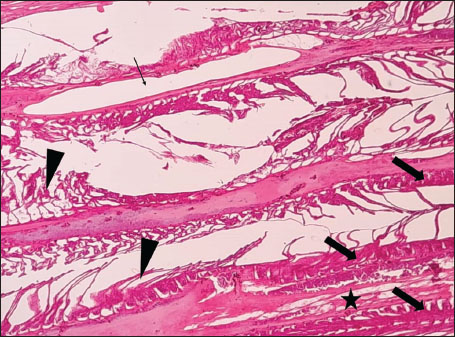

ABSTRACTBackground: The Mediterranean Sea has undergone significant ecological changes in recent decades, partly due to the introduction of non-native species. Lagocephalus sceleratus is an invasive Lessepsian species widely distributed in the Mediterranean, increasingly abundant along the Libyan coast, and potentially exposed to chronic environmental stressors. This species represents an important model for baseline pathological assessment in newly colonized marine environments. Aim: This study provides a descriptive histopathological assessment of kidney and gill tissues in adult L. sceleratus to document baseline tissue alterations without inferring direct environmental or pollution-related causation. Methods: A total of 150 adult specimens were collected from four Libyan coastal locations. Tissues were processed using standard histological techniques and evaluated semi-quantitatively (+, ++, +++) for lesion severity. Lesion severity grades were converted into ordinal numerical data and summarized using descriptive statistical approaches only. Results: Kidney tissues exhibited tubular degeneration, Bowman’s capsule dilatation, vascular congestion, extensive melanomacrophage centers (MMCs), and inflammatory lesions. Gill tissues showed disorganization of secondary lamellae, epithelial hyperplasia, edema, aneurysmal dilatations, vascular congestion, and MMC proliferation, some of which were associated with histologically observed parasitic structures. Conclusion: The observed alterations represent descriptive baseline tissue changes and should not be interpreted as direct evidence of pollution or specific environmental stressors. These findings provide reference data for future comparative pathological and ecological studies. Keywords: Lagocephalus sceleratus, Kidney, Gills, Histopathology, Melanomacrophage centers, Invasive species, Mediterranean Sea. IntroductionIn recent decades, the Mediterranean Sea has undergone profound ecological changes driven by the arrival and establishment of non-native marine species. Among these, Lagocephalus sceleratus has emerged as one of the most impactful Lessepsian migrants, due to its rapid geographic expansion, high ecological adaptability, and the presence of the potent neurotoxin tetrodotoxin in its tissues. This species has been widely documented to alter local fish communities, affect fisheries, and pose public health risks, making it an important target for biological and environmental assessment across the region (Katikou et al., 2022; Christidis et al., 2024). Fish are widely recognized as sensitive biological organisms in aquatic ecosystems, particularly in coastal habitats that are exposed to anthropogenic pressures such as industrial effluents, agricultural runoff, and untreated wastewater (Pinna et al., 2023). Among fish organs, the gills and kidneys are commonly regarded as sensitive to environmental stress, as they respond to physiological and pathological changes under environmentally suboptimal conditions. The gills, due to their large surface area and continuous exposure to surrounding water, are often the first tissues to exhibit structural alterations when fish encounter pollutants (Shahid et al., 2022). Histopathological changes in gills observed in polluted environments include epithelial lifting, lamellar fusion, hyperplasia, increased mucous cell density, and focal necrosis, which collectively reflect early physiological stress and potential compromise of respiratory function (Osman, 2010; Shahid et al., 2022). Similarly, the kidneys play crucial roles in osmoregulation, excretion of metabolic waste, and detoxification, making them highly vulnerable to chronic or systemic toxic effects (Wahidi et al., 2025). Documented renal lesions associated with chemical exposure include tubular deterioration, glomerular shrinkage, interstitial edema, and infiltration of inflammatory cells. These structural alterations often coincide with underlying biochemical disruptions, such as oxidative stress, impaired detoxification pathways, and activation of apoptotic mechanisms (Bernet et al., 1999; Authman, 2015). Despite the growing body of research on the ecological and toxicological implications of L. sceleratus, detailed histopathological assessments of this species remain scarce, especially in the southern Mediterranean basin, where environmental conditions and pollution profiles may differ from those in other regions. To date, detailed tissue-level studies of L. sceleratus from the southern Mediterranean are lacking, which limits the understanding of how this invasive species responds physiologically to local environmental stressors (Shakman et al., 2019; Ulman et al., 2021; Mohmmed et al., 2023). Accordingly, the present study aims to provide a comprehensive descriptive evaluation of histopathological changes in the kidneys and gills of L. sceleratus. The study is designed as a baseline histopathological assessment, focusing on tissue-level alterations without establishing causal links to environmental pollution or physicochemical stressors. By documenting structural aberrations and pathological features, this study contributes reference data for future monitoring and comparative studies in Mediterranean coastal ecosystems. Materials and MethodsSample designA total of 150 adult specimens of L. sceleratus, including both sexes, were collected from four Libyan coastal locations: Talamitha (n=39), Susah (n=34), Ain El-Ghazala (n=30), and Khalij Al-Bambah (n=47). Fish ranged in total length from 51 to 66 cm and in weight from 1.5 to 3.5 kg. Only apparently healthy adults were included, while juveniles were excluded to avoid age-related histopathological variation. Sampling was conducted opportunistically with assistance from local fishermen. All specimens were collected within a comparable seasonal window to minimize seasonal histopathological variability. Sex was recorded when possible; however, sex-based histopathological comparisons were not performed, as this was beyond the descriptive scope of the study. Fish were transported on ice at +4°C and examined in the Pathology Laboratory, Faculty of Veterinary Medicine, Omar Al-Mukhtar University (Mohmmed et al., 2023). Specimens were collected from a range of depths (0.5–70 m), with the majority from shallow waters (<10 m) and a subset (approximately 50 fish) from deeper locations (>30 m). Environmental physicochemical parameters such as temperature, salinity, and dissolved oxygen were not measured; therefore, no direct associations between histopathological findings and environmental variables were assessed. Tissue processing and histopathological examinationTissue specimens were fixed in 10% neutral buffered formalin for 24 hours. Following fixation, the samples were transferred to 70% ethanol for storage at room temperature. Subsequently, the tissues were processed for routine histopathological examination following standard procedures (Paul and Chanda, 2017). Paraffin embedding was performed, and 5 µm-thick sections were prepared using a microtome. Sections were stained with hematoxylin and eosin (H&E) and examined under a light microscope. Photomicrographs of representative lesions were captured using a high-resolution digital camera. Histopathological alterations were evaluated using a semi-quantitative scoring system adapted from Hose et al. (1996), Moshaie-Nezhad et al. (2021), and Alshailabi et al. (2023), where lesion severity was graded as mild (+), moderate (++), or severe (+++). Lesion severity grades (+, ++, +++) were converted into ordinal numerical values (1–3) for descriptive summarization of lesion severity. Due to the descriptive baseline nature of the study and the absence of a reference control group, inferential statistical comparisons were not emphasized or applied. Lesion severity scores were therefore summarized descriptively to avoid overinterpretation of the findings. Scoring was performed independently by two experienced observers, and representative lesions were confirmed across three sections per organ to ensure consistency. Tissues with visible parasitic structures were described separately from non-parasitized tissues to avoid conflating parasite-associated lesions with non-specific tissue alterations. The functional implications of the observed lesions were interpreted in accordance with Flores-Lopes and Thomaz (2011). Ethical approvalAll animal experiments conducted in this study were approved by the Ministry of Higher Education & Scientific Research and the Libyan National Committee for Biosafety & Bioethics, Libya. All procedures were performed in accordance with the relevant ethical guidelines, with session number 21/CH/25, dated 26/05/2021. ResultsHistopathological examination of the kidneyHistopathological examination of the kidney tissues of L. sceleratus revealed multiple alterations. Prominent melanomacrophage centers (MMCs), necrotic areas, dilatation of Bowman’s capsules, and vacuolar degeneration were observed (Fig. 1), associated with interstitial lymphohematopoietic tissue (Fig. 2). Dilated and congested blood vessels and extensive MMCs were also noted (Fig. 3). Renal degeneration surrounding lymphohematopoietic tissue, large clusters of MMCs, and thickened, congested vessel walls within fibrotic areas were evident (Fig. 4). Atrophic renal degeneration with necrotic and vacuolar changes was observed (Fig. 5). Severe inflammatory infiltration of lymphatic cells and granulomas with necrotic centers, surrounded by fibrous tissue, was detected (Figs. 6–7).

Fig. 7. Histopathology of the kidney in an adult L. sceleratus showed the atrophic renal degeneration (stars), dilatation of Bowman’s capsules (thick arrows), and a granuloma (head arrow). ×400 H&E. Histopathological examination of the gillsThe gill sections of adult L. sceleratus exhibited multiple structural alterations. Secondary lamellae showed marked disorganization, while gill filaments displayed club-shaped deformities and occasional aneurysmal dilatations (Fig. 8). Vascular congestion with telangiectatic changes and proliferation of MMCs were also observed (Figs. 9–10). Edematous changes in primary lamellae, separation of the epithelial layer, lamellar aneurysms, and epithelial hyperplasia were documented (Figs. 10–11). Focal damage to secondary lamellae, disruption of lamellar architecture, presence of lamellar aneurysms, and unidentified parasitic structures were observed (Fig. 12). Pronounced vascular congestion and dilatation of lamellae due to red blood cell accumulation were noted (Fig. 13).

Fig. 11. Histopathology of the gills in an adult L. sceleratus showing edema in primary lamellae and epithelial detachment (thin arrow), curling of secondary lamellae (head arrows), congestion/telangiectasia (star), and epithelial hyperplasia (thick arrows). ×40 H&E.

Fig. 12. Histopathology of the gills in an adult L. sceleratus showing the damage to secondary lamellae and lamellar disorganization (thick arrows), lamellar aneurysm (head arrows), and unidentified parasites (thin arrows). ×40 H&E.